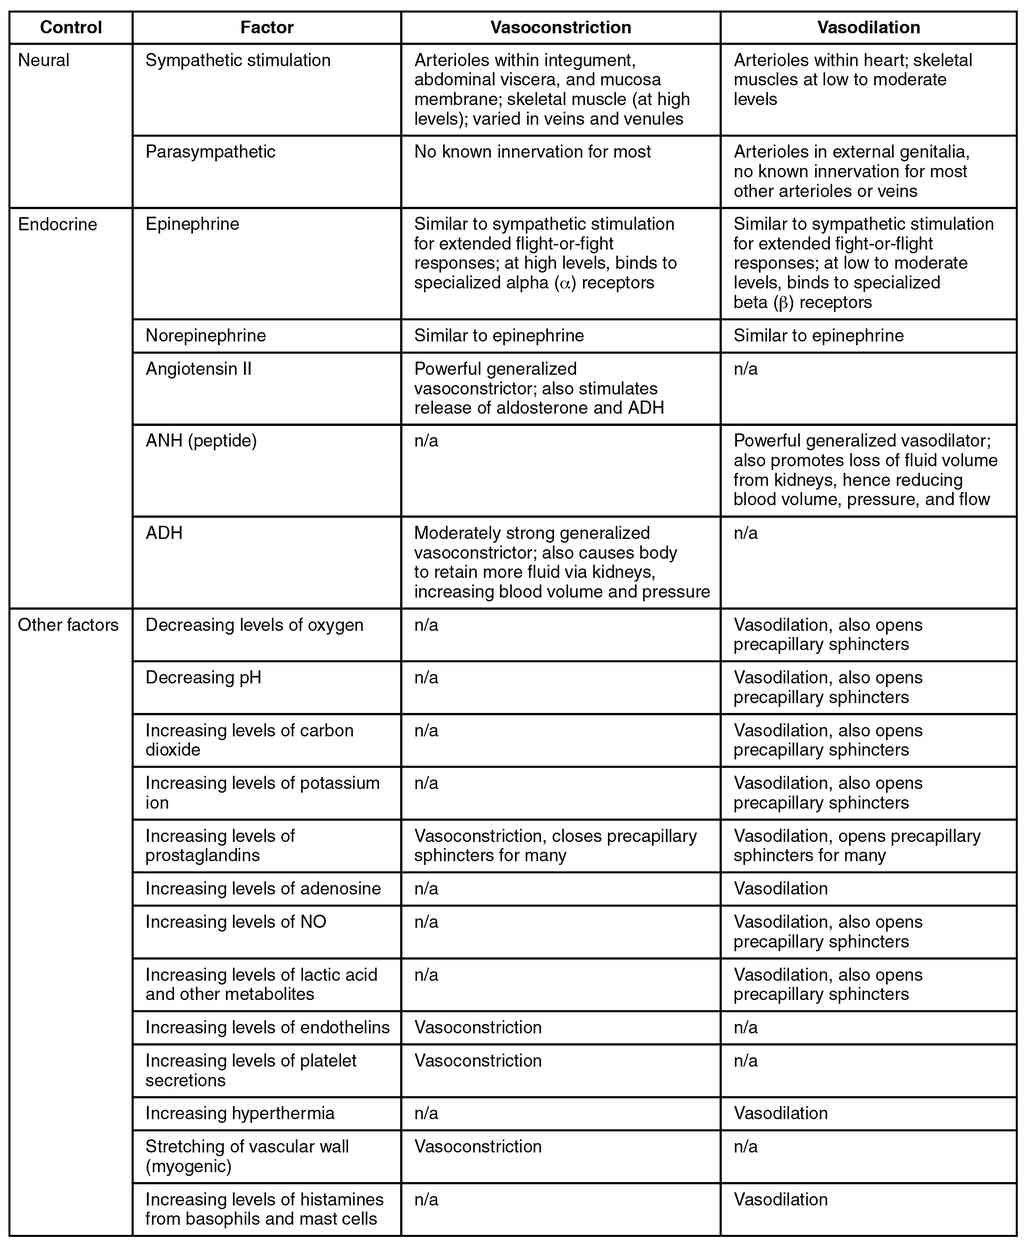

This page is under construction. For now, it is just a resource of the images found in the OpenStax Anatomy and Physiology Handbook. It wil slowly change into a revision tool. Each slide has a number. Use this to refer to the slide. When completed, it will have an unlabelled section, with labelled slides in parallel. On the unlabelled slides, write your answer and use the labelled slide to assess yourself. Keep track by also noting the number on each slide. Improvement at each attempt is important, more so than full marks on a first attempt.